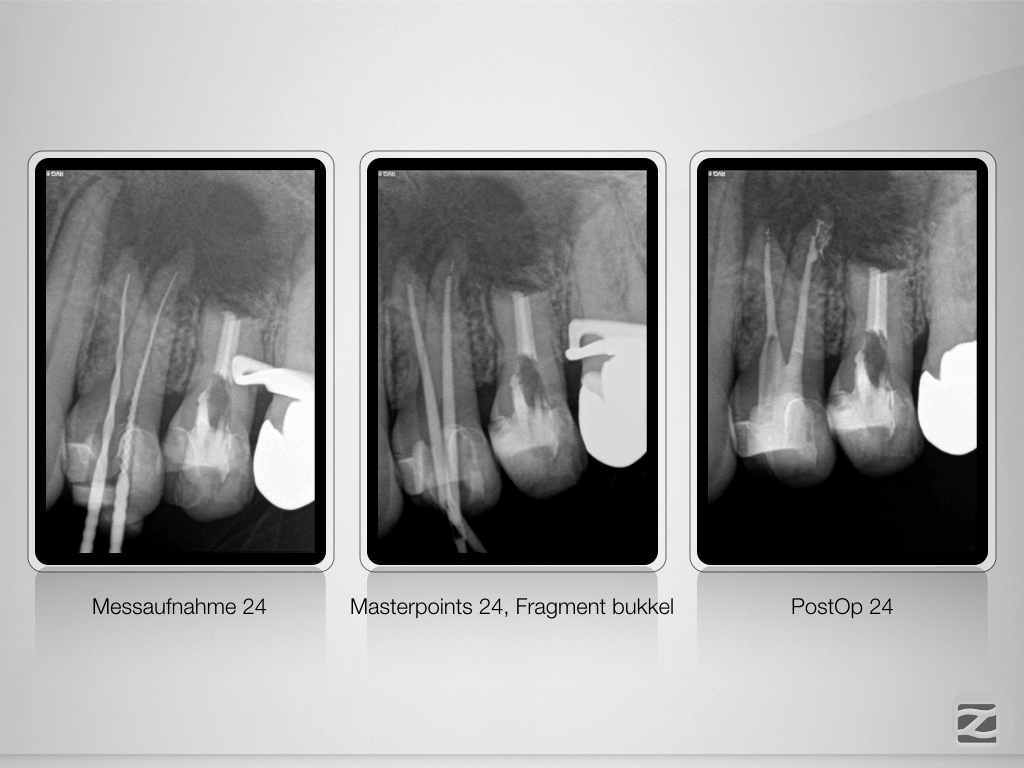

Große Aufhellung, langes Recall